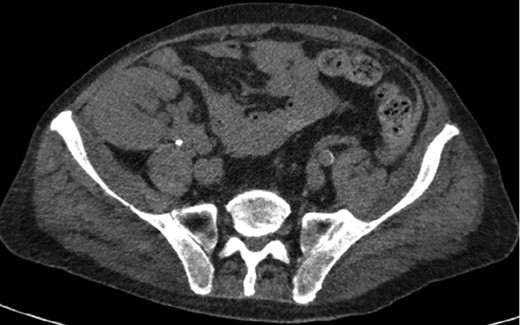

A 68-year-old male with history of living donor renal transplant presented to the ED with acute onset of profound weakness, fatigue, left upper quadrant abdominal pain, hypotension and lactic acidosis. On exam, he exhibited mild left upper quadrant and epigastric tenderness without evidence of peritonitis. CT imaging demonstrated splenomegaly with a large splenic hematoma measuring 15.7 × 9.2 × 12 cm and associated hemoperitoneum (Figs 1–3). In addition, innumerable osseous lytic lesions were identified. Given these findings, emergent surgical consultation was obtained and his coagulopathy reversed. He remained hypotensive despite resuscitation, thus was taken for laparotomy. Upon abdominal entry, a large amount of old clot was evacuated. The abdomen was packed in all quadrants in the standard fashion. Upon removal of the left upper quadrant packs, active hemorrhage began to well from the region of the spleen which was mobilized and removed via splenectomy. Upon gross inspection, the spleen was hyperemic and abnormally indurated, with an avulsion type injury extending several centimeters across the inferior pole. There was no evidence of pseudoaneurysm or other gross pathology. Given the patient was mildly hypothermic and coagulopathic with continued oozing from the retroperitoneum, the decision was made to pack the splenic fossa and place a temporary wound vac. The patient was transported to the ICU for resuscitation and brought back to the OR the next morning for re-exploration and closure. Despite hemodynamic stabilization, he underwent a prolonged hospitalization complicated by atrial fibrillation, renal allograft failure, VAP, and ultimately PEA arrest progressing to asystole. He died 6 weeks following splenectomy. The pathology from the spleen revealed splenomegaly with parenchyma that was replaced with amorphous and acellular eosinophilic material. Histologic staining (Thioflavin-T) was positive for amyloidosis, AL-type. Oncology was consulted based on these findings with concern for lymphoproliferative disorder given osseous findings on CT, splenic pathology, and history of immunosuppression. Bone marrow biopsy was subsequently obtained which showed more than 50% atypical plasma cells/plasma blasts (CD138+; PAX5 negative; EBV (EBER) negative) and no amyloidosis, consistent with multiple myeloma. Urine showed Bence-Jones protein. Serum immunofixation studies were remarkable for a monoclonal IgG lambda gammopathy, consistent with the diagnosis of AL amyloidosis associated with systemic myeloma.

Coronal CT imaging demonstrating splenomegaly with splenic capsule rupture at the inferior pole with heterogeneous fluid in the paracolic gutters and perisplenic region suggestive of hemoperitoneum.